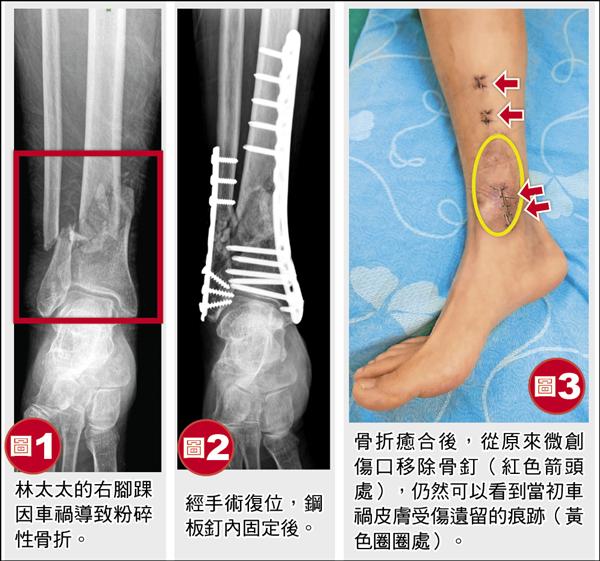

林太太一年前因騎車發生車禍,腳踝被車輪輾過,造成小腿遠端脛腓骨粉碎性骨折,被送到醫院急診,骨折處需要接受開刀治療(圖1)。

骨科醫師建議使用微創手術做骨折部位的鋼板內固定(圖2),術後傷口恢復情形良好,住院一星期就順利出院了。

門診追蹤一年後,在骨折癒合後,再將鋼板由原本手術小傷口取出(圖3)。